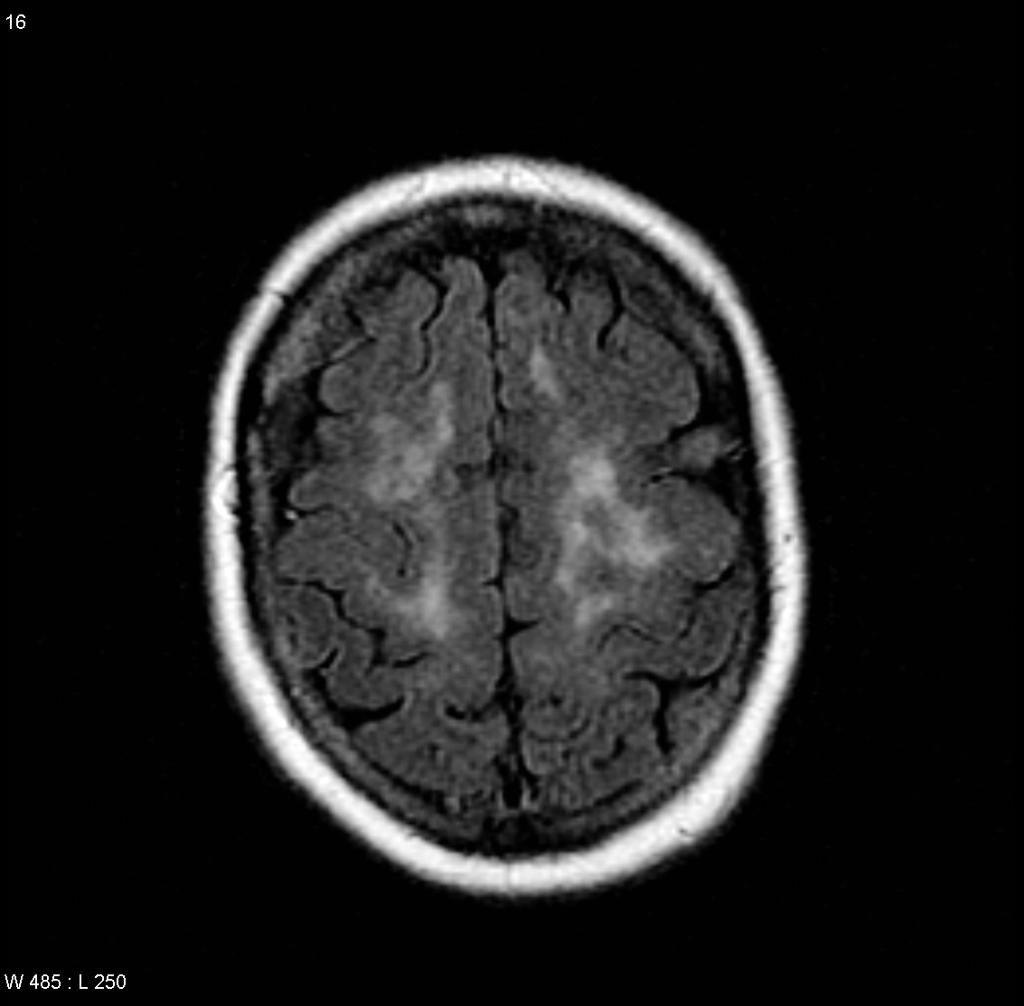

SYNDROME DE SUZAC

Microangiopathie cochléo-encéphalo-rétinienne

• Hypersignal T2 et FLAIR du corps calleux

• Petite taille

• Bien délimités

• De localisation centrale, non callosofuges

• Pas d’atrophie calleuse

• Prises de contraste rares

• Diffusion restreinte